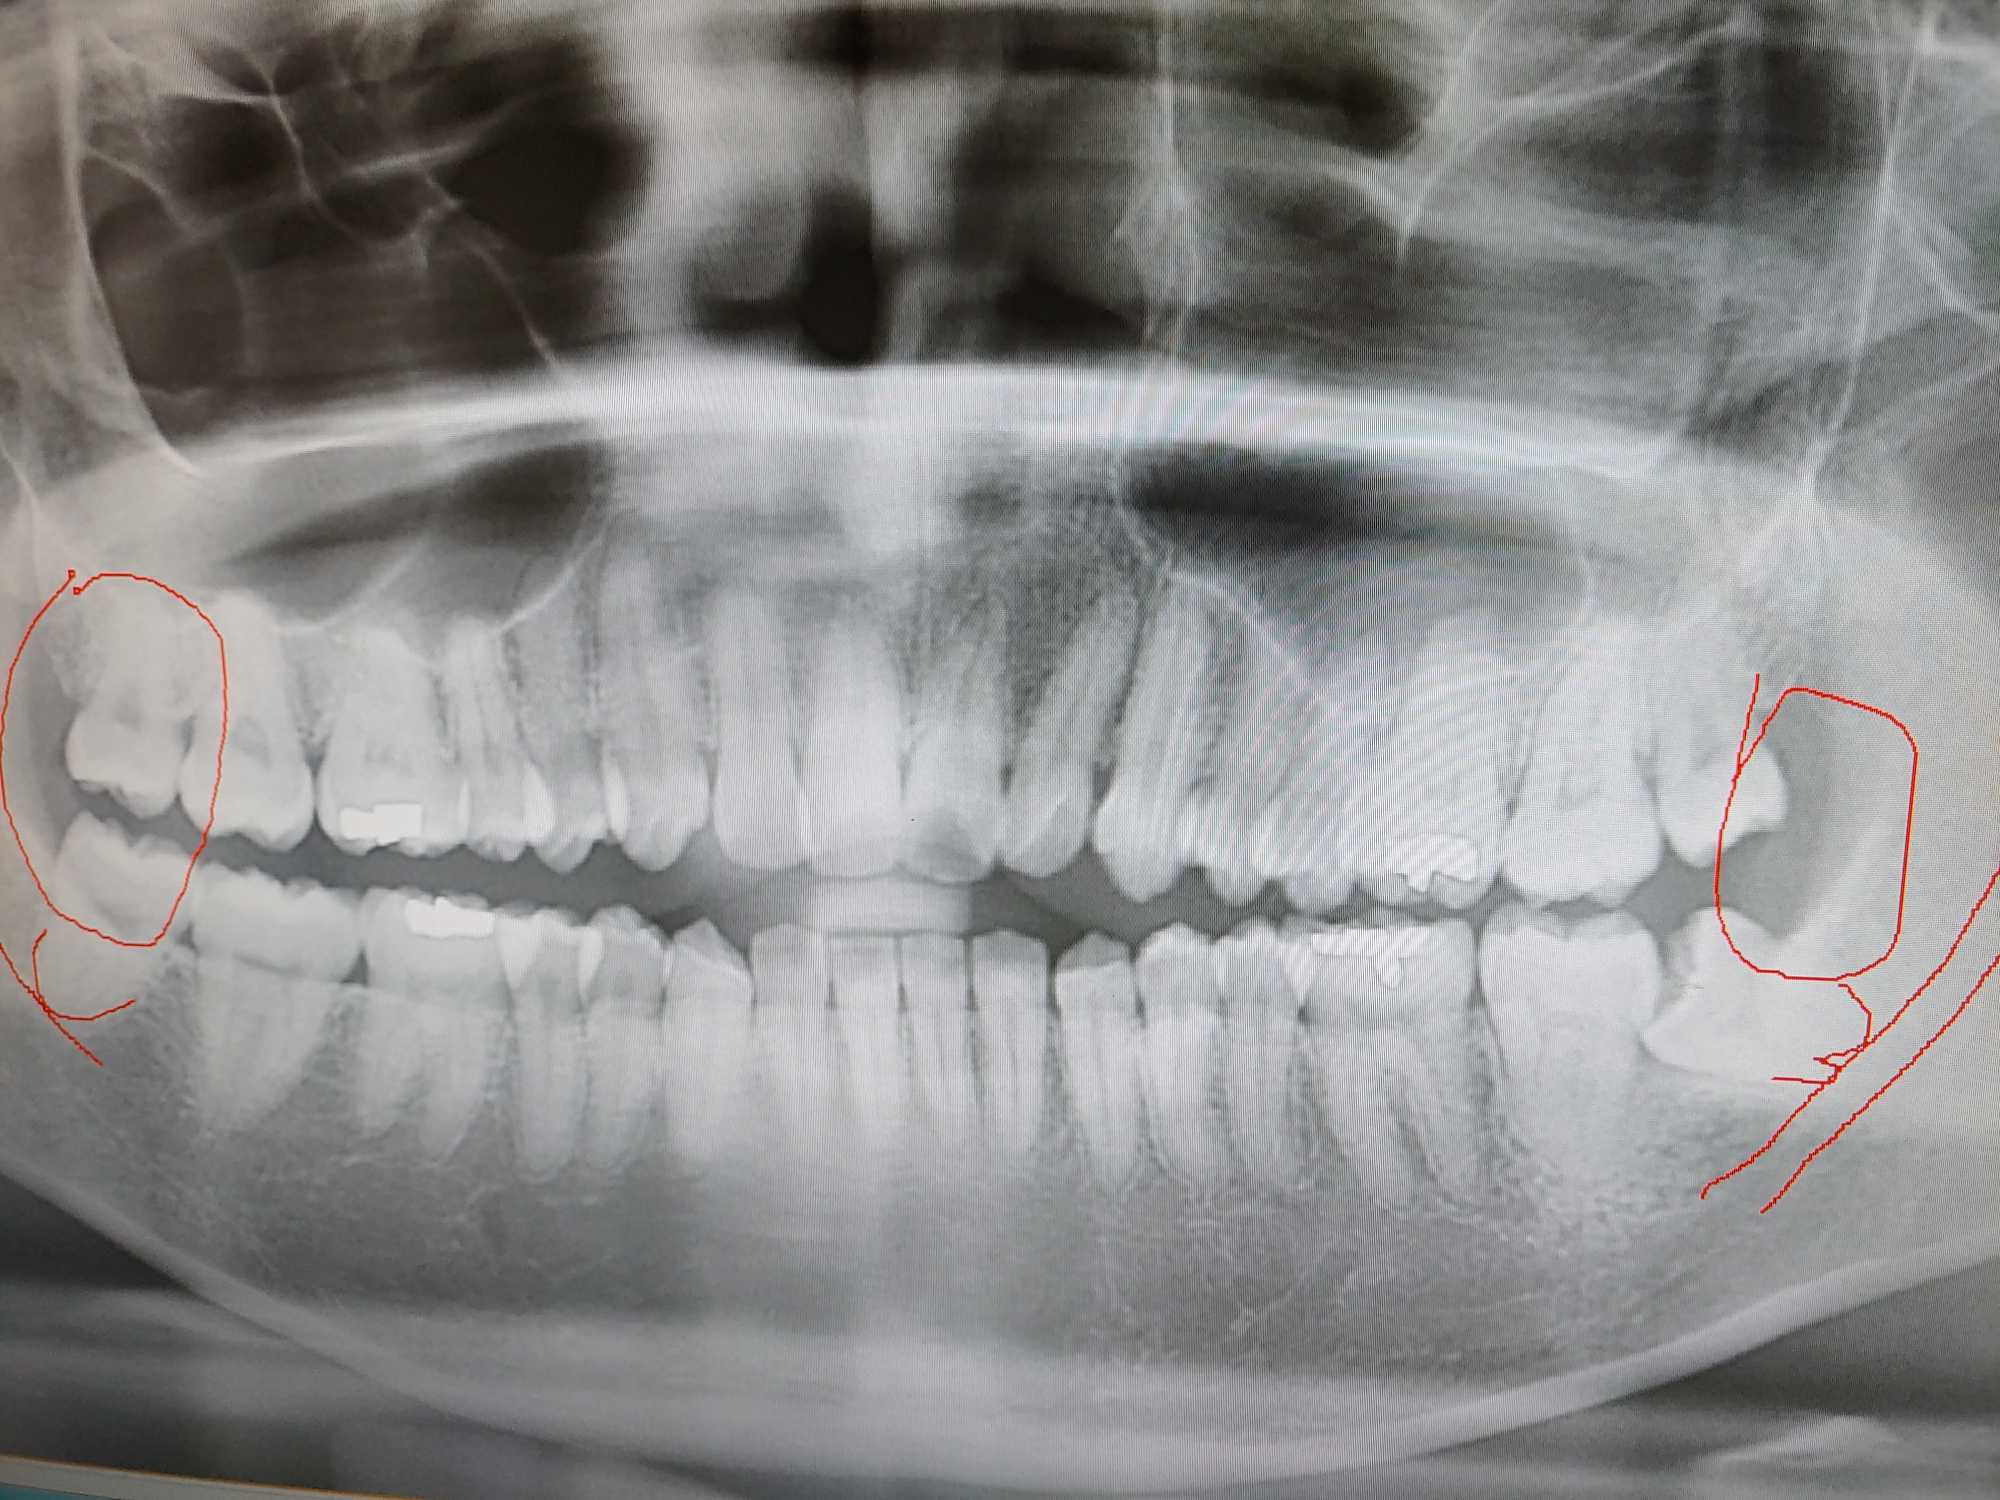

안녕하세요. 사랑니로 인한 통증이 심하여 발치하려고 합니다. 동네 치과에 갔더니 총 사랑니가 위에 2개 아래 2개 있는데 신경과 맞닿아있는 사랑니가 2개 있어 발치하다 신경을 건드릴 경우 입주변이 마비될 수가 있다고 진단해주셨습니다. 이런 가능성을 책임져 줄 수 있는 병원은 의원급은 없다고 보면 되고, 큰 종합병원이나 대학병원 가야한다고 하셨는데 정말 그렇게 심각한 상태인가요? 사진 첨부해드립니다. 답변 부탁드립니다. 0